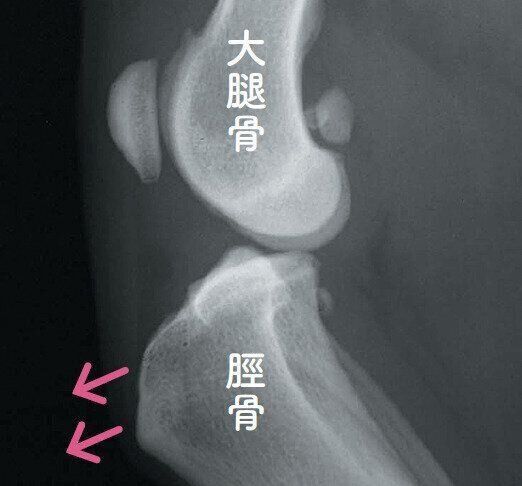

前十字靭帯断裂のレントゲン写真

発症した膝のエックス線写真。骨をつなぐ靭帯が切れたため、大腿骨に対して脛骨が矢印の方向(前方)にずれています。参考・写真/「いぬのきもち」2025年12月号『サインを見逃さないで!冬に気をつけたい犬の痛い!病気』より 枝村一弥先生提供

ひざの中にある前十字靭帯が切れる病気で、痛みを伴います。季節を問わず発症しますが、急に冷えこむようになった時季にひざに負荷がかかるような運動をさせると、発症するリスクが一気に高まります。肥満や加齢でひざが弱くなっている犬は、特に注意が必要です。